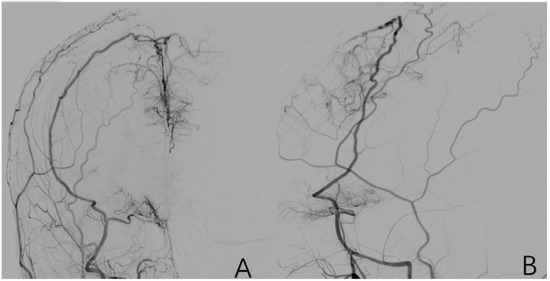

2.3.10. Factor 5 Posterior Circulation Compensation

2.3.11. Factor 6 Unstable Compensation

2.3.12. Factor 7 Extracranial Arterial Compensation